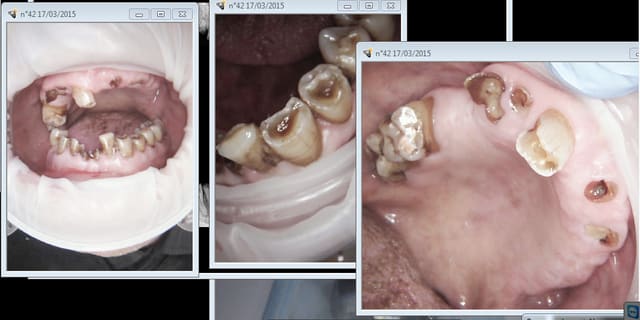

Merci aux participants de ce post qui permettent de le faire progresser par leurs réponses et questions. J’ai choisi une forme interrogative au sujet pour ouvrir une conception du champ d’application du protocole de MCI proposé, hors des dogmes.

pano initiale et planche 3D montrant qu'en fait les molaires ne tenaient quasi plus que par les racines palatines...